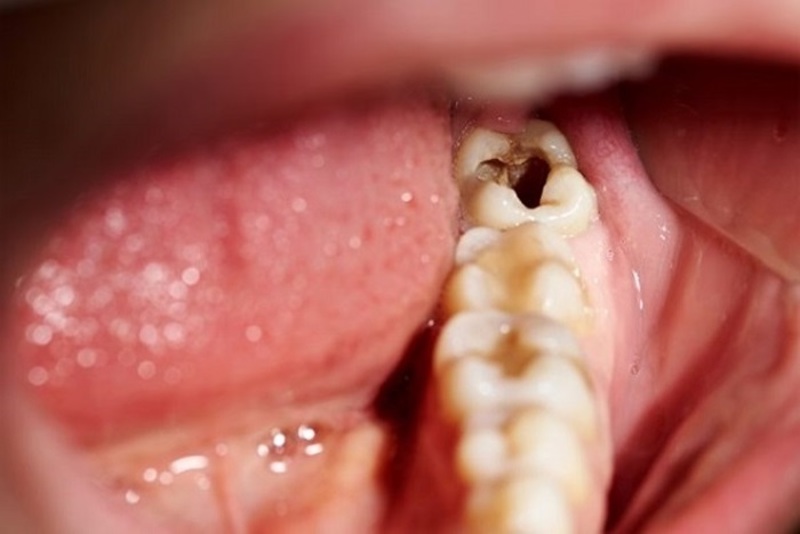

Từ đó dẫn đến những tình trạng mọc sai vị trí của răng khôn như là: mọc lệch, mọc chồng lên răng khác, răng mọc chen chúc nhau, răng mọc ngầm, răng mọc ngang, răng mọc ngược vào xương hàm…gây ra những cơn đau, khó chịu kéo dài, sưng tấy, đỏ viêm ở vùng lợi răng mọc.

Ngoài ra, răng số 8 nằm ở vị trí trong cùng của hàm răng – vị trí sâu trong khoang miệng nên khó khăn trong việc vệ sinh sạch sẽ hàm răng, khiến vi khuẩn sâu răng dễ dàng xâm nhập, làm hư hại đến những chiếc răng của bạn. Chính vì vậy nên chúng ta phải nhổ răng khôn bỏ đi.

Đây là biến chứng thường gặp nhất vì sự tích tụ thức ăn và những vi khuẩn răng miệng tại vị trí răng khôn mọc lên gây viêm nhiễm tại chỗ – ở quanh vùng răng mọc. Người mọc răng thường thấy đau nhói, hôi miệng, sưng phù ở vùng lợi mọc răng khôn khiến cho việc há miệng khó khăn, thâm chí còn có thể chảy mủ ở vùng lợi bị viêm.

Răng số 8 mọc lệch thường làm hỏng răng bên cạnh là răng số 7. Tình trạng mọc lệch hình thành nên khe hở giữa răng khôn và răng số 7 dễ làm kẹt lại thức ăn, khiến khó vệ sinh, lâu ngày chắc chắn gây ra sâu răng. Khi răng khôn mọc lệch làm ép vào răng bên cạnh làm tiêu biến mất một phần thân và chân răng này.